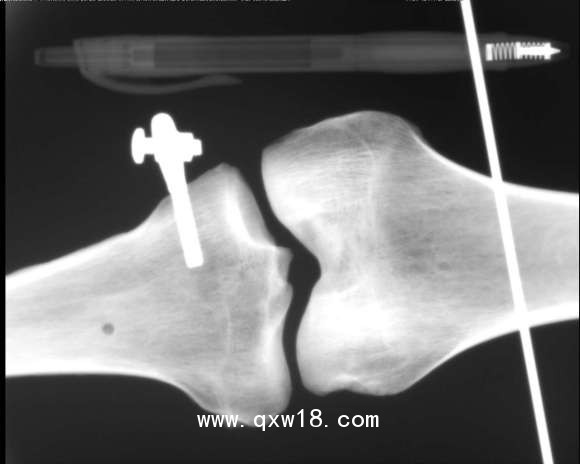

動物x光機

動物、海洋生物檢測儀,采用R160數(shù)字成像系統(tǒng)成像,?0.3微焦點射線管集約束散射線,數(shù)字成像,圖像清晰.儀器全數(shù)字化軟件操作功能;正反選圖像、圖像放大縮小、左右旋轉(zhuǎn),前后旋轉(zhuǎn)、翻轉(zhuǎn)、數(shù)字化高清灰度專業(yè)圖像采集、千兆網(wǎng)端有線和無線連接,電腦即時成像、存儲和即時打印檢測效果圖片。

XDX-DF160B型?動物、海洋生物檢測儀;主要針對動物,海洋生物、魚類檢測;同時還可用于:玩具、蟲草、斷針、金屬異物等檢測